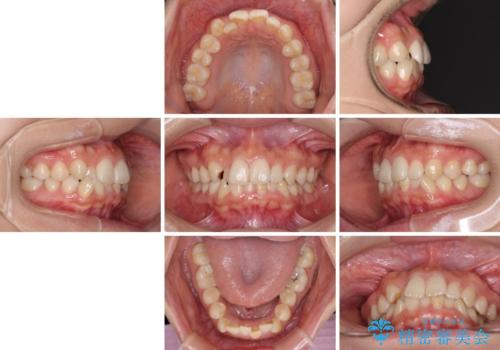

- 前歯のクロスバイトを気にして来院された患者様です。

治療方法としては、マウスピース矯正(インビザライン)でもワイヤー矯正でも、何でも対応可能ですが、自己管理の煩わしさがなく、治療期間の目処を立てやすい表側のワイヤー矯正にて治療を行うこととしました。